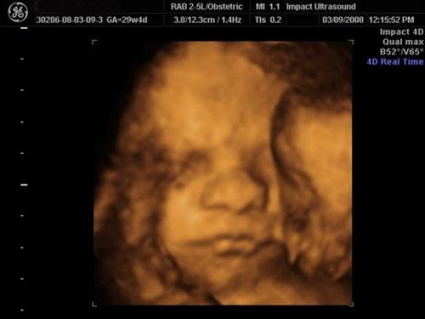

3D pics!

Oh Kel...how amazing! Your little boy!!!!

Posted by 2Pisces 3/9/08 9:51PM

Great pics of your peanut...won't be long now!

Posted by SweetCin 3/9/08 6:35PM